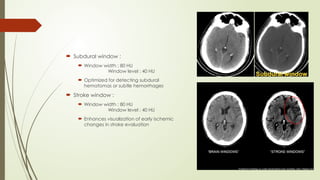

 Subdural window :

 Window width : 80 HU

Window level : 40 HU

 Optimized for detecting subdural

hematomas or subtle hemorrhages

 Stroke window :

 Enhances visualization of early ischemic

changes in stroke evaluation